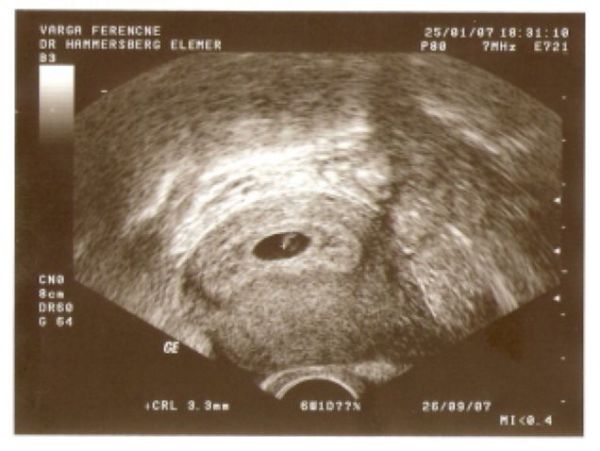

nagyon gratulálok! Nem semmi vagy! Kiváncsi leszek majd, hogy mikor is fogant méretei szerint ez a bébi!!!!